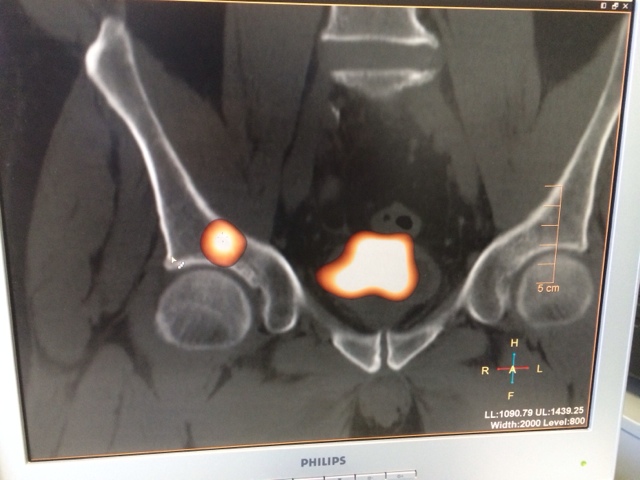

They have a whole-body scan (hybridized with full-dose CT) before being discharged. This is an image of a patient with thyroid cancer metastasis to the pelvis.